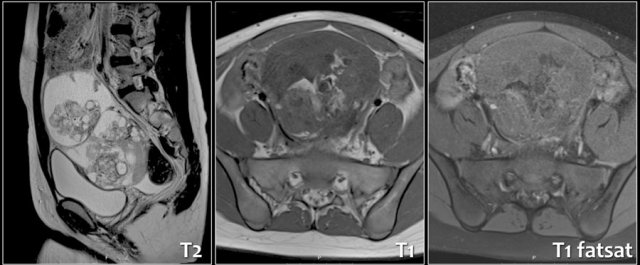

Ovarian teratoma

Ovarian teratomas are composed of ecto-, meso-, and endoderm. They can become apparent as a large painless mass, but they can also twist, especially when the diameter is > 5 cm and cause an acute abdomen. Some are incidental findings.

On US a cystic mass can be seen with calcifications. Sometimes a fluid-fluid level is seen, by the separation of watery fluids and fat.

If the tumor contains lots of bone, hair, or calcifications, it is echogenic and sonographic diagnosis is challenging.

A Rokitansky nodule refers to a solid mass attached to the wall of a cyst, containing hair, bone, teeth or fat.

A plain abdominal film can sometimes show teeth or bone.

CT and especially MRI can provide a clear answer to the nature of the lesion.

On MRI some solid parts display high signal on T1, with low signal on fat suppressed sequences due to the fat content in the tumor.

Most of the solid parts enhance after Gadolineum.

Pathology demonstrated a immature teratoma.